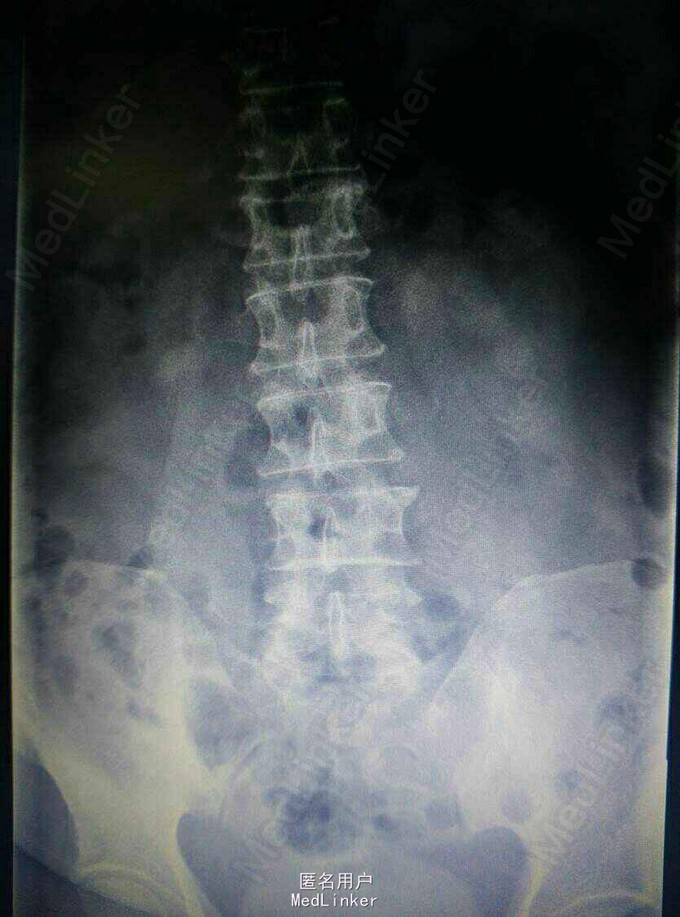

患者,男,39岁,因“左下肢放射性痛一月,加重一周”入院。患者一月前劳累后出现左下肢放射性疼痛,卧床休息后稍微缓解。一周前搬重物后再次加重。

查体:脊柱无明显畸形,腰背部无压痛,左小腿外侧、后侧及足底触痛觉减退,左下肢肌力4级,左下肢直腿抬高试验40度阳性,右下肢(–)。

诊断:L45及L5/S1 双节段椎间盘突出(左侧),辅助检查:MRI提示: L45及L5/S1 双节段椎间盘突出,压迫左侧神经根。